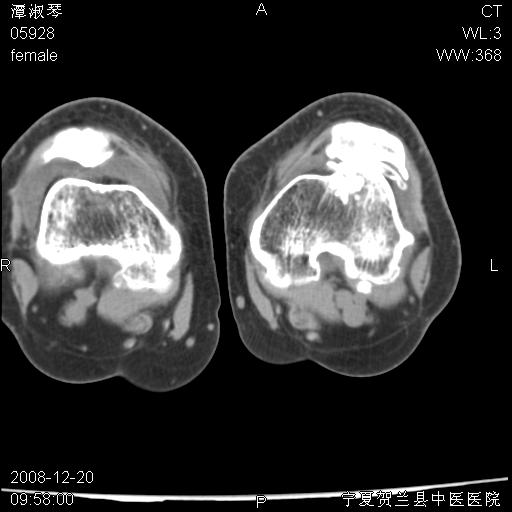

标题: CT17526:请各位看看是啥?

内生软骨瘤?骨梗死?

考虑内生软骨瘤可能性大

考虑-----骨梗死+退变

支持骨梗死,退行性骨关节病,膝关节积液.

考虑骨梗死可能性大

骨梗死可能性大

左股骨下段骨梗死。双膝退变。

左胫骨下端松质骨及髓腔内可见点片状高密度灶,骨皮质无明显膨胀及变薄。病变范围较长。支持骨梗死,退行性骨关节病,膝关节积液